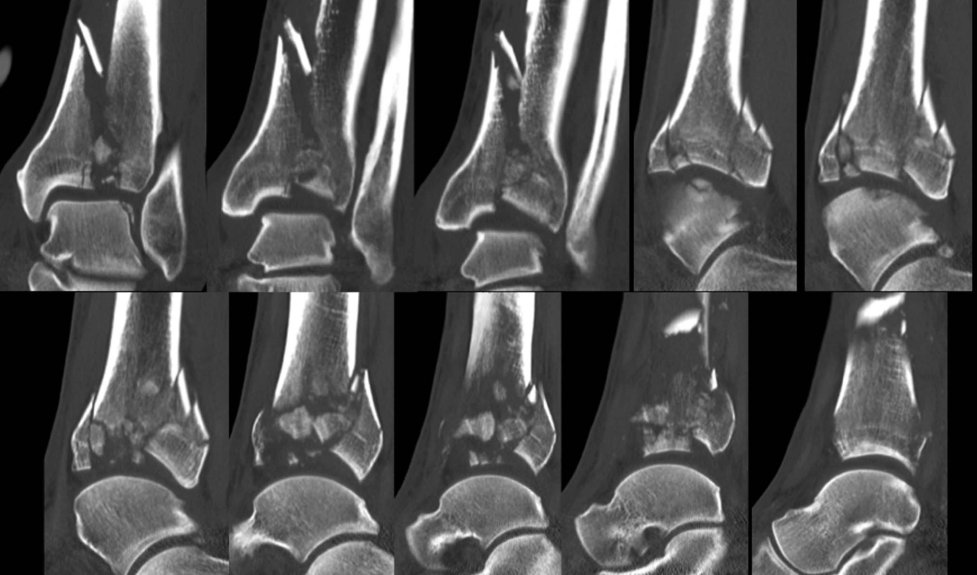

Pilon骨折的手术治疗目的,是恢复胫骨远端关节面的平整,恢复下肢力线以及胫距关节面的良好匹配,在术前CT扫描的准确评估下,采用合适的手术入路治疗。

扩大入路适用于胫骨三柱与干骺端或骨干完全分离的骨折,此类骨折关节面无任何部分与骨干相连,通常伴随广泛的关节粉碎。直至最近,仍无单一切口可同时显露内侧柱和外侧柱:传统AO前内侧入路可良好显露内侧柱,但难以显露外侧柱和Tillaux-Chaput骨折块;前外侧入路虽能良好显露外侧柱,但无法充分显露内侧柱。扩大入路通过单一切口可完全显露内侧柱和外侧柱,并可在内侧/外侧或前方放置接骨板。对于近端延伸的骨折,接骨板可通过开放关节切口经皮下从远端向近端置入。该入路适用于涉及多个柱的骨折,但对于单柱骨折(43-B型)或关节外骨折(43-A型)无需采用。